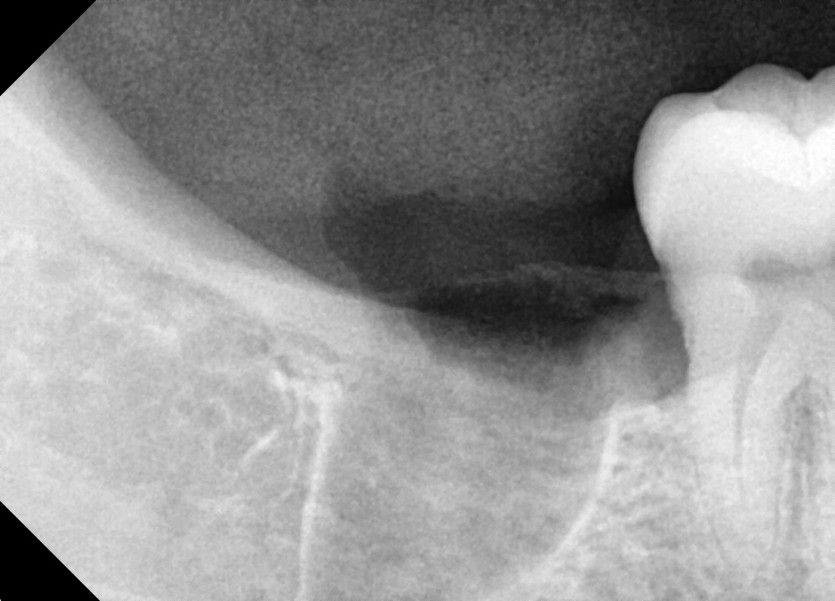

#48 사랑니 발치

구강 외과 전문의가 당일 발치했습니다.